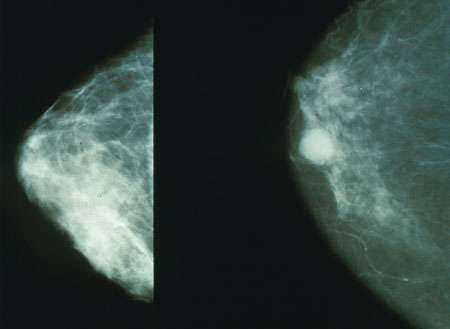

【免疫系统在乳腺癌的传播中起着矛盾的作用】免疫系统在乳腺癌的传播中起着矛盾的作用。一些免疫细胞有助于转移,而其他细胞可以被激活以加强化疗的效果。Kelly Kersten 在她的博士研究中发现了这一现象。

虽然癌症治疗一直在改善,但乳腺癌仍然是女性死亡的主要原因之一,其中大多数死亡归因于肿瘤的扩散。“我们知道免疫系统的细胞在这里发挥作用,但是确切的作用方式仍然未知,”Kersten 解释说。她在阿姆斯特丹的荷兰癌症研究所进行的研究旨在澄清这一过程。